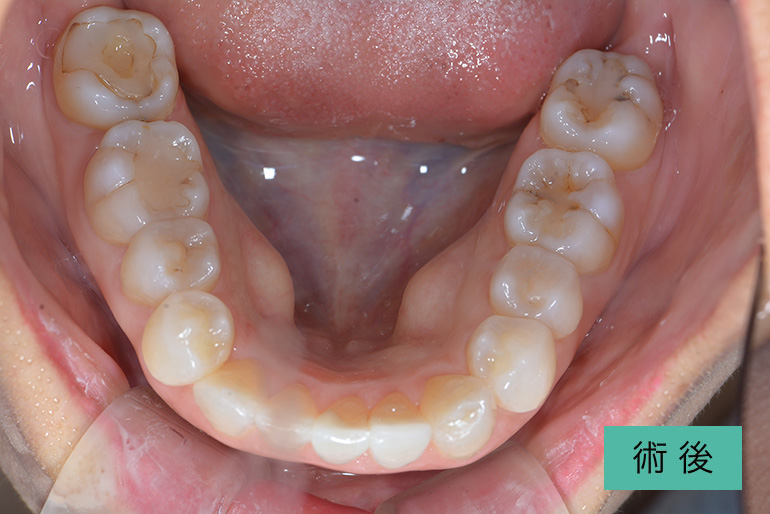

インプラント④

| 治療内容 | 入れ歯が合わなくてずっと噛みにくい。 下顎の入れ歯は不安定になるので、下顎の歯が無いところはインプラント治療をする。 上顎の入れ歯は患者さんが許容されてますので、保険治療の入れ歯で治療をする。 下顎を安定して治療すれば、上顎の入れ歯はどの歯科医師が作成しても噛める入れ歯を作ることは簡単。 将来、当院まで来院できなくなったとしても、どんな先生が治療しても上手くいくはずなので心配がない。 治療後、9年経過してますが上顎の入れ歯を作成するのみで対応できています。 |

|---|---|

| 治療期間・回数 | 半年、30回 |

| 費用(税込) | インプラント+セラミック冠 ¥2,596,000 ※自由診療 上顎入れ歯 ※保険診療 |

| リスク・副作用 | 出血、痛み、外科的治療、下歯槽神経麻痺 |